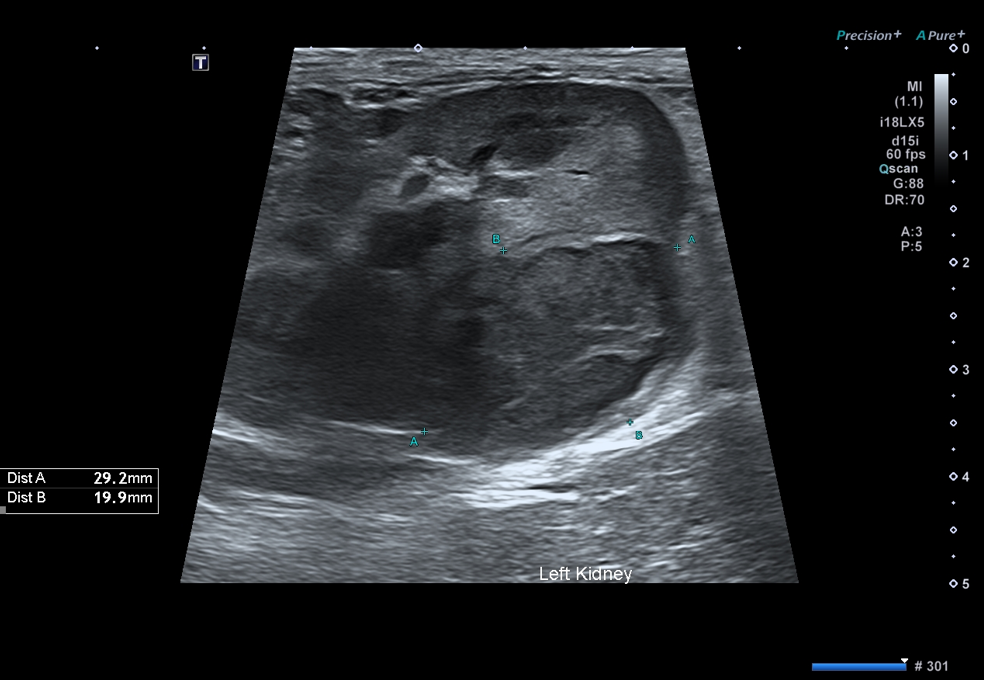

따라서 우선적으로 영상 검사를 통해 주요 원인을 감별하고자 복부 방사선 촬영과 초음파 검사를 진행하였습니다.

그러나 복부 초음파 검사에서 좌측 신장 후극에약 30 × 20 mm크기의 종괴가확인되었습니다.